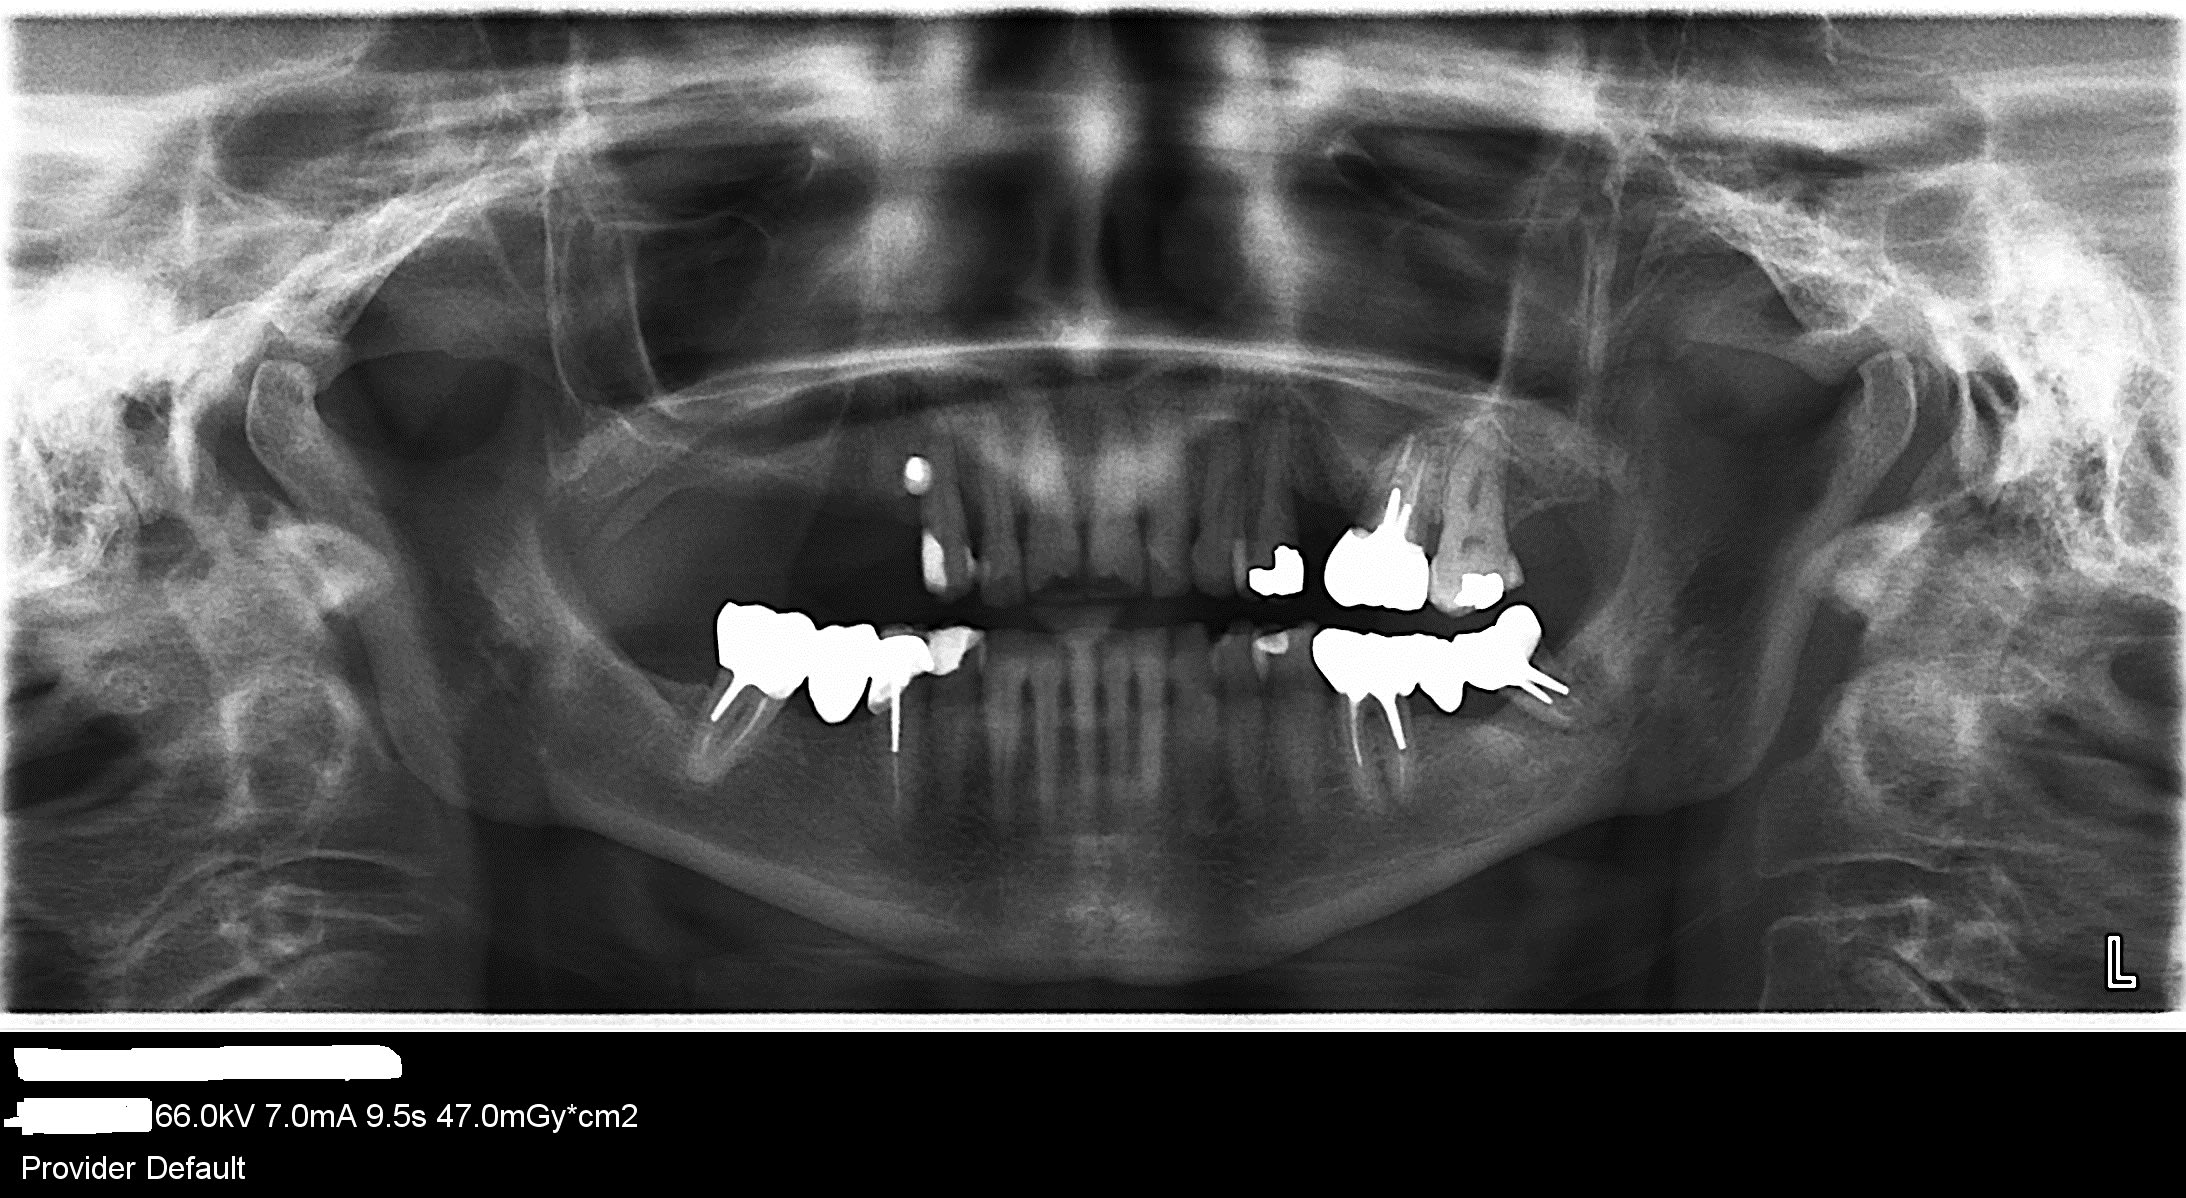

que feriez vous? j'ai 13 24 26 supports de crochets de l'ancien stellite qui bougent beaucoup. J'ai pour l'instant fait une contention collée de 13 à 24, n'ayant pas sauté le pas de les extraire . Mais faudrait pas porter le stellite car il traumatise ces trois dents lorsqu'il est en fonction. J'ai pensé à extraire tout de même ces trois dents mobiles stade 2/3, et faire un bridge de contention de 12 à 23. avec attachements extra coronaires en 12 et 23 et nouveau stellite .

J'éviterai les attachements... Compliqué casse gueule et nécessitant de solidariser les dents... In fine si y'en a une qui merde tu perds tout...

Reste sur l'idée de contention et vois si tu peux faire un truc avec des fraisages

Merci , donc tu ferais des couronnes fraisées sur certaines incisives et sur 27?

Fraisages sur les dernière dents à la place des obturation... T'as déjà la taille précuite...

Après faut voir l'oclusion et ce que tu veux faire des antérieures....